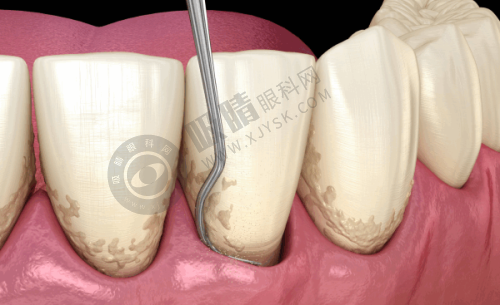

浙江大学医学校附属第二医院口腔科拥有进口的综合治疗牙椅30张,精良的数字化牙科摄片系统。这些精良的设备为口腔疾病的诊断和治疗提供了有力的支持,能够更精细地为患者进行口腔检查和治疗。